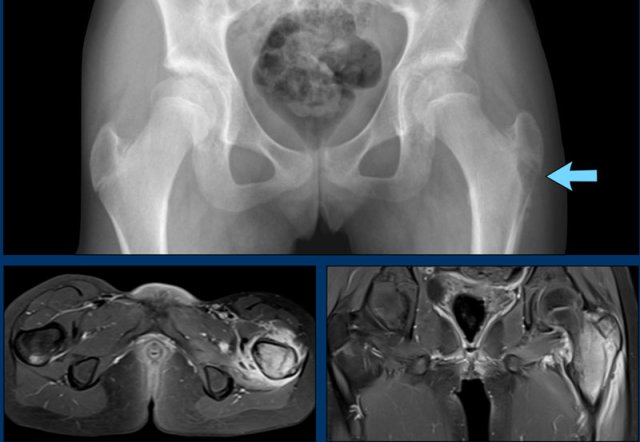

This radiograph of the pelvis is of a patient with tuberculous arthritis of the left hip joint.

There is subtle joint space narrowing with some subchondral sclerosis of the left hip.

These radiographic findings are nonspecific and most likely would be the result of osteoarthritis..

Continue with the MRI...

Much to everyone's surprise there were multiple abscesses.

When abscess formation is this extensive and the clinical findings are minimal, always think of tuberculous arthritis.

The diagnosis of tuberculous arthritis was made by joint aspiration.